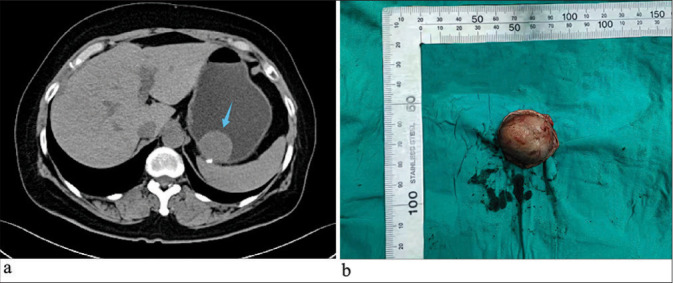

Although gastrointestinal stromal tumor (GIST) can present with various histological characteristics, GIST mimicking perineurioma has not been previously reported. We present the case of a 47-year-old woman diagnosed with GIST after laparoscopic resection of a stomach tumor near the lesser curvature of the gastric body close to the cardia. Morphological features resembled a perineurioma. c.1504_1509 (p.A502_Y503) duplication was found in exon 9 of kinase insert domain receptor (c-KIT). This specific mutation is associated with constitutive activation of the c-KIT, which is crucial in the pathogenesis of GIST. Such unique histological characteristics broaden our understanding of the morphological diversity within GISTs and underscore the importance of considering an extended differential diagnosis when encountering atypical gastrointestinal tumors. This rare presentation may challenge conventional diagnostic criteria and could influence therapeutic strategies, emphasizing the need for comprehensive histological and molecular assessments in patient management.